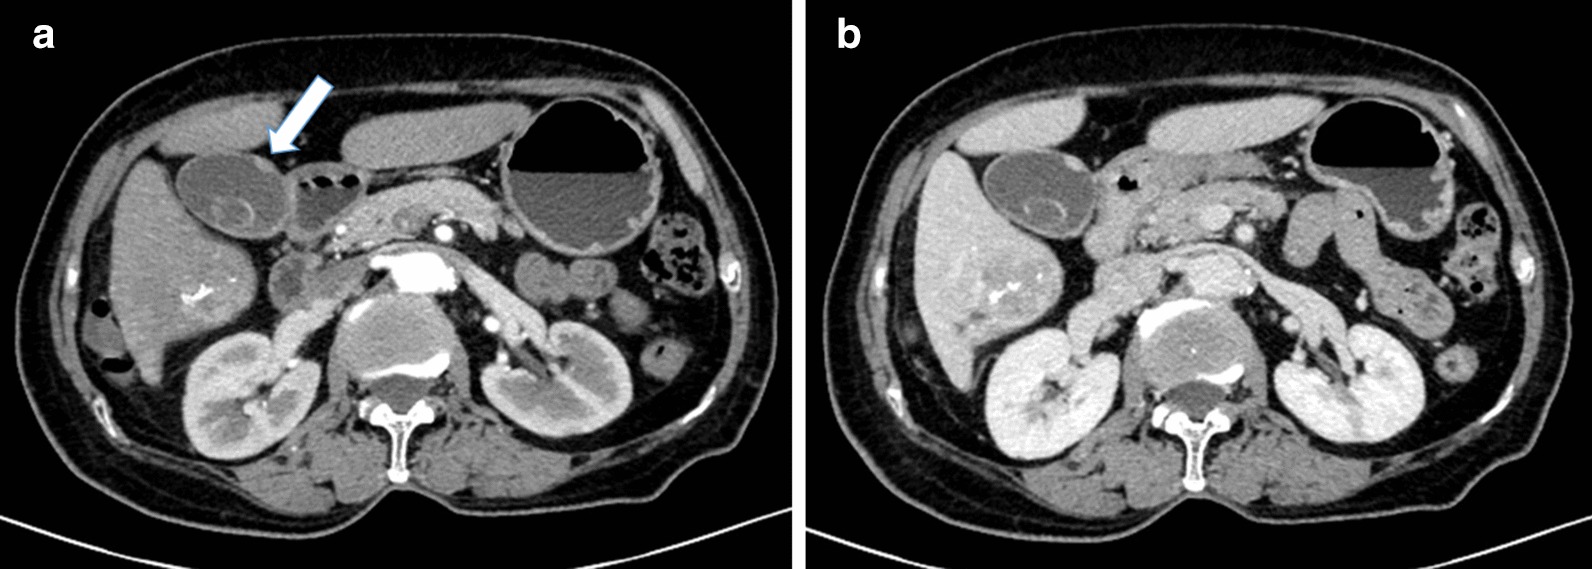

Fig. 3.

Abdominal CT images after TACE to observe the gallbladder mainly. a Arterial phase (white arrow indicating nodular thickening in the gallbladder wall), b venous phase

The preoperative diagnosis of MPC can be difficult, and gallbladder cancer with hepatic metastasis or liver cancer with gallbladder invasion can be mistakenly diagnosed. In this case, except for weakness and inappetence, no other discomfort was observed. A sharp rise in the serum level of AFP is usually linked with liver cancer, while CEA, CA19-9 and CA125 are linked with gallbladder adenocarcinoma, but these levels were normal in this patient. The giant tumor in the right lobe of the liver was noticed first so the tiny lesions in the gallbladder wall were nearly neglected. Six weeks after TACE was performed, an enhanced CT scan clearly demonstrated nodular thickness of the gallbladder wall up to 0.5 cm. To some extent, unobvious symptoms, insensitive serum examinations and atypical radiological manifestations made the diagnosis delayed and vague. Even though these assessments may mislead us to consider the possibility a primary HCC with satellite nodules in the gallbladder may exist, we finally denied this possibility because the two specimens showed totally different histopathological morphologies; moreover, the immunohistochemical markers revealed AFP(+) in liver specimens and AFP(−) in gallbladder specimens.